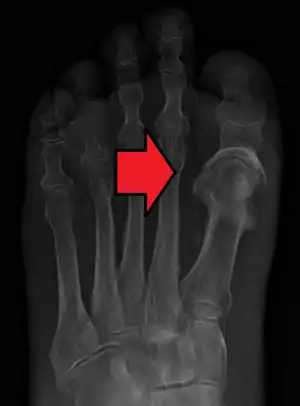

Radiographs and CT are the initial method of diagnosis, but are not sensitive and only moderately specific for the diagnosis. They can show the cortical destruction of advanced osteomyelitis, but can miss nascent or indolent diagnoses.[23]

Diagnosis of osteomyelitis is often based on radiologic results showing a lytic center with a ring of sclerosis.[13] Culture of material taken from a bone biopsy is needed to identify the specific pathogen;[26] alternative sampling methods such as needle puncture or surface swabs are easier to perform, but cannot be trusted to produce reliable results.[27][28]